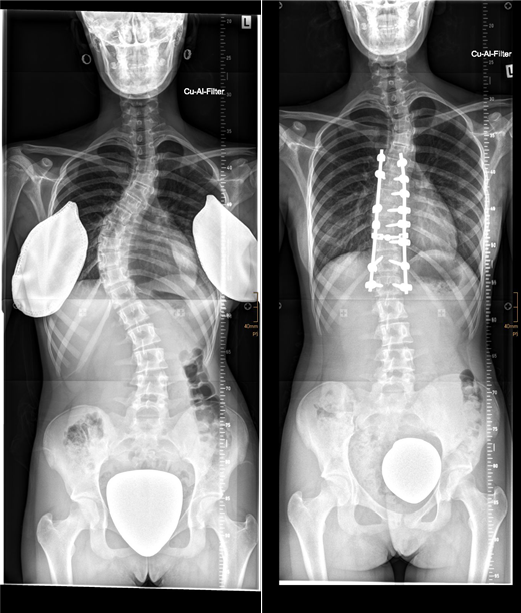

Skoliose_Korsett

Bild 1: Ein Beispiel für die Behandlung einer Skoliose im Bereich der Brust- und Lendenwirbelsäule mit einem Korsett. Die Krümmung kann fast vollständig korrigiert werden.